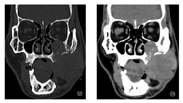

磁共振口腔及颈部平扫增强(图2):左颊部可见一长T1长T2信号肿块灶,增强后呈轻中度部均匀强化,较大层面大小约51 mm×52 mm,肿块向上突入左侧上颌窦,与邻近上颌骨及上牙槽分界不清,左眼眶外侧壁呈长T1长T2信号,增强后可见强化,向内与舌体分界不清,向外与左侧咬肌分界不清,左侧翼外肌T2WI信号稍增高,双侧颈部多发小淋巴结。

CT颌面部平扫增强三维成像(图3):左颊部巨大肿块灶,较大层面大小约54 mm×39 mm,其内部密度不均,CT值约为37HU-66HU,肿块向上突入左侧上颌窦,向内侧与舌体分界欠清晰,向外侧与左侧咬肌分界不清,邻近左侧眼眶、下侧壁、左侧上颌骨、上牙槽、左侧额突受侵犯,骨质吸收破坏征象:考虑颊癌复发可能性大。